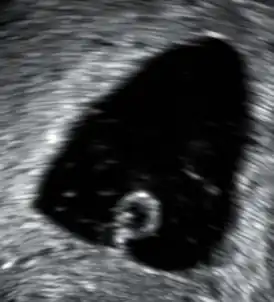

Выкидыш может быть обнаружен при помощи специальной ультразвуковой аппаратуры. При поиске микроскопических патологических симптомов выкидыша следует посмотреть снимок. К микроскопическим относятся ворсинки, трофобласт, части плода. Также можно выполнить генетические тесты для поиска ненормальных хромосом. Роль в морфологическом исследований заключается в выявлении и изучении морфологических изменений в материале получаемый при спонтанных абортах.

Выкидыш может быть обнаружен во время УЗИ или посредством серии замеров уровня хорионического гонадотропина человека (ХГЧ). Существуют медицинские способы для прекращения беременности с документально подтверждённой нежизнеспособностью плода, который не был изгнан естественным путём.